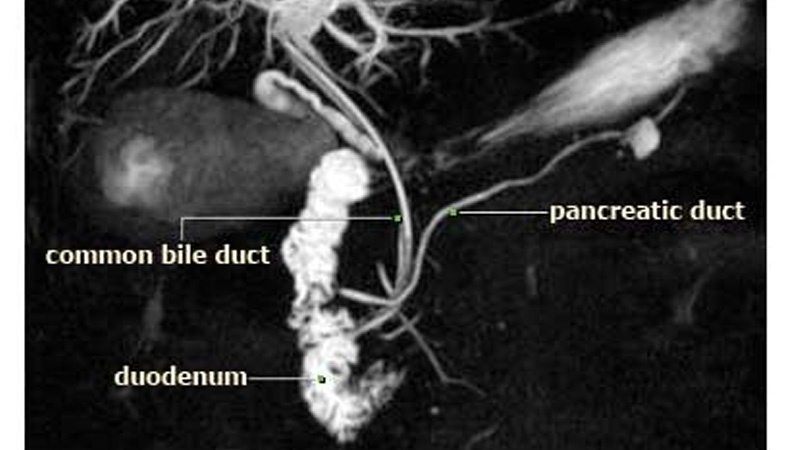

Kan tahlili, besin maddelerinin hastanın sindirim sistemi tarafından doğru emilmediğini ve vücuda alınmadığını gösteren dışkıdaki yağ seviyesi testi, bilgisayar yardımlı tomografi, safra taşı ve pankreas iltihabının incelenmesi hedefi ile karın boşluğu sonografisi, pankreas kanalı ve safra kesesi kanalındaki tıkanıkların ve iltihapların belirlenmesi için baş vurulan songorafi-endsokopi ve de pankreatit teşhisi için MR da bu doğrultuda önerilen teşhis yöntemleridir.

Pankreas hastalıklarına tanı koyulması için muayeneye ihtiyaç duyulmaktadır. Bu muayene fiziki olabilir. Bu çerçevede doktor karnın orta bölümüne dokunarak kitle şeklindeki engebeli oluşumları arar. Doktor pankreas hastalıklarının diğer belirtilerini de inceleyebilir. Ayrıca detaylı görüntüler sunan bilgisayar yardımlı tomografiden de yararlanabilir. Bu çerçevede görüntülerin daha net olması için hastanın vücuduna belli sıvılar da enjekte edilebilir. MR çekmek de bir başka teşhis yöntemidir. Manyetik dalgalar hastanın karnından net görüntüler bize sunarlar. MR türlerinden sayılan MRCP'ye de pankreas, karaciğer ve safra kesesine özel bir yöntem olarak baş vurulabilir.